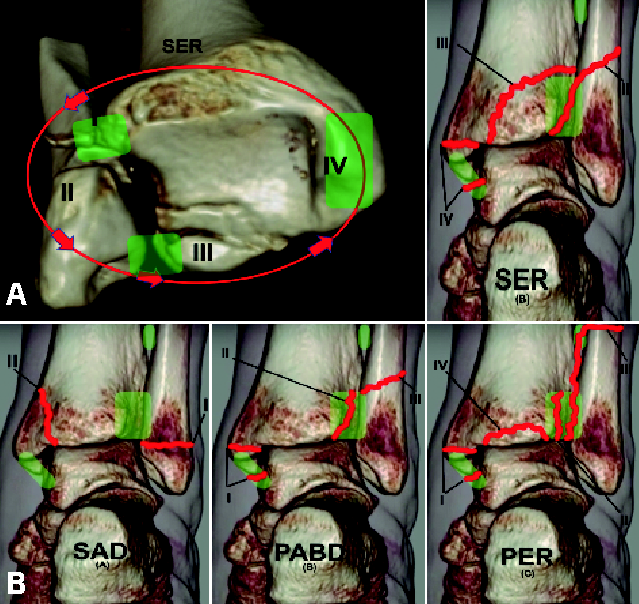

Cada estadio implica un paso más en la magnitud de la fuerza y engloba las lesiones de los anteriores; así, por ejemplo, el esquema de las lesiones de tipo supinación-rotación externa (las más frecuentes) puede observarse en la Figura 1A, en sentido horario para el pie derecho y antihorario para el izquierdo.

Muchos aspectos de ambas clasificaciones pueden interdigitarse y complementarse (Figura 1B), encontrando importantes analogías entre ambas, de forma que las fracturas de supinación-aducción corresponden por mecanismo de acción y hallazgos morfológicos a las Weber A, las de supinación-rotación externa y pronación-abducción a las Weber B y las que implican pronación-rotación externa a las Weber C.

Figura 1. A: secuencia de las lesiones en estadios SER; B: clasificación de Lauge-Hansen y su relación con la clasificación de Weber.